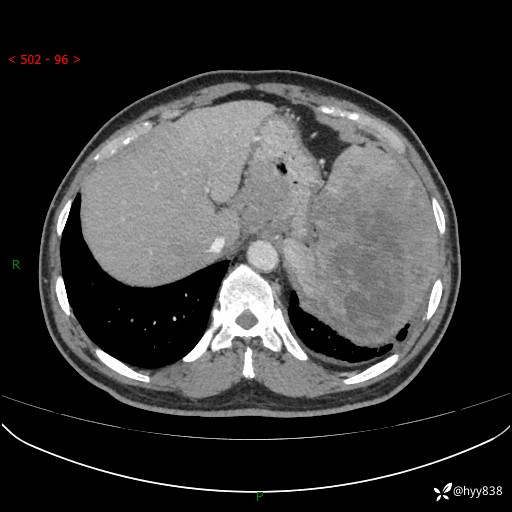

上腹部CT平扫

增强(动脉期+静脉期)